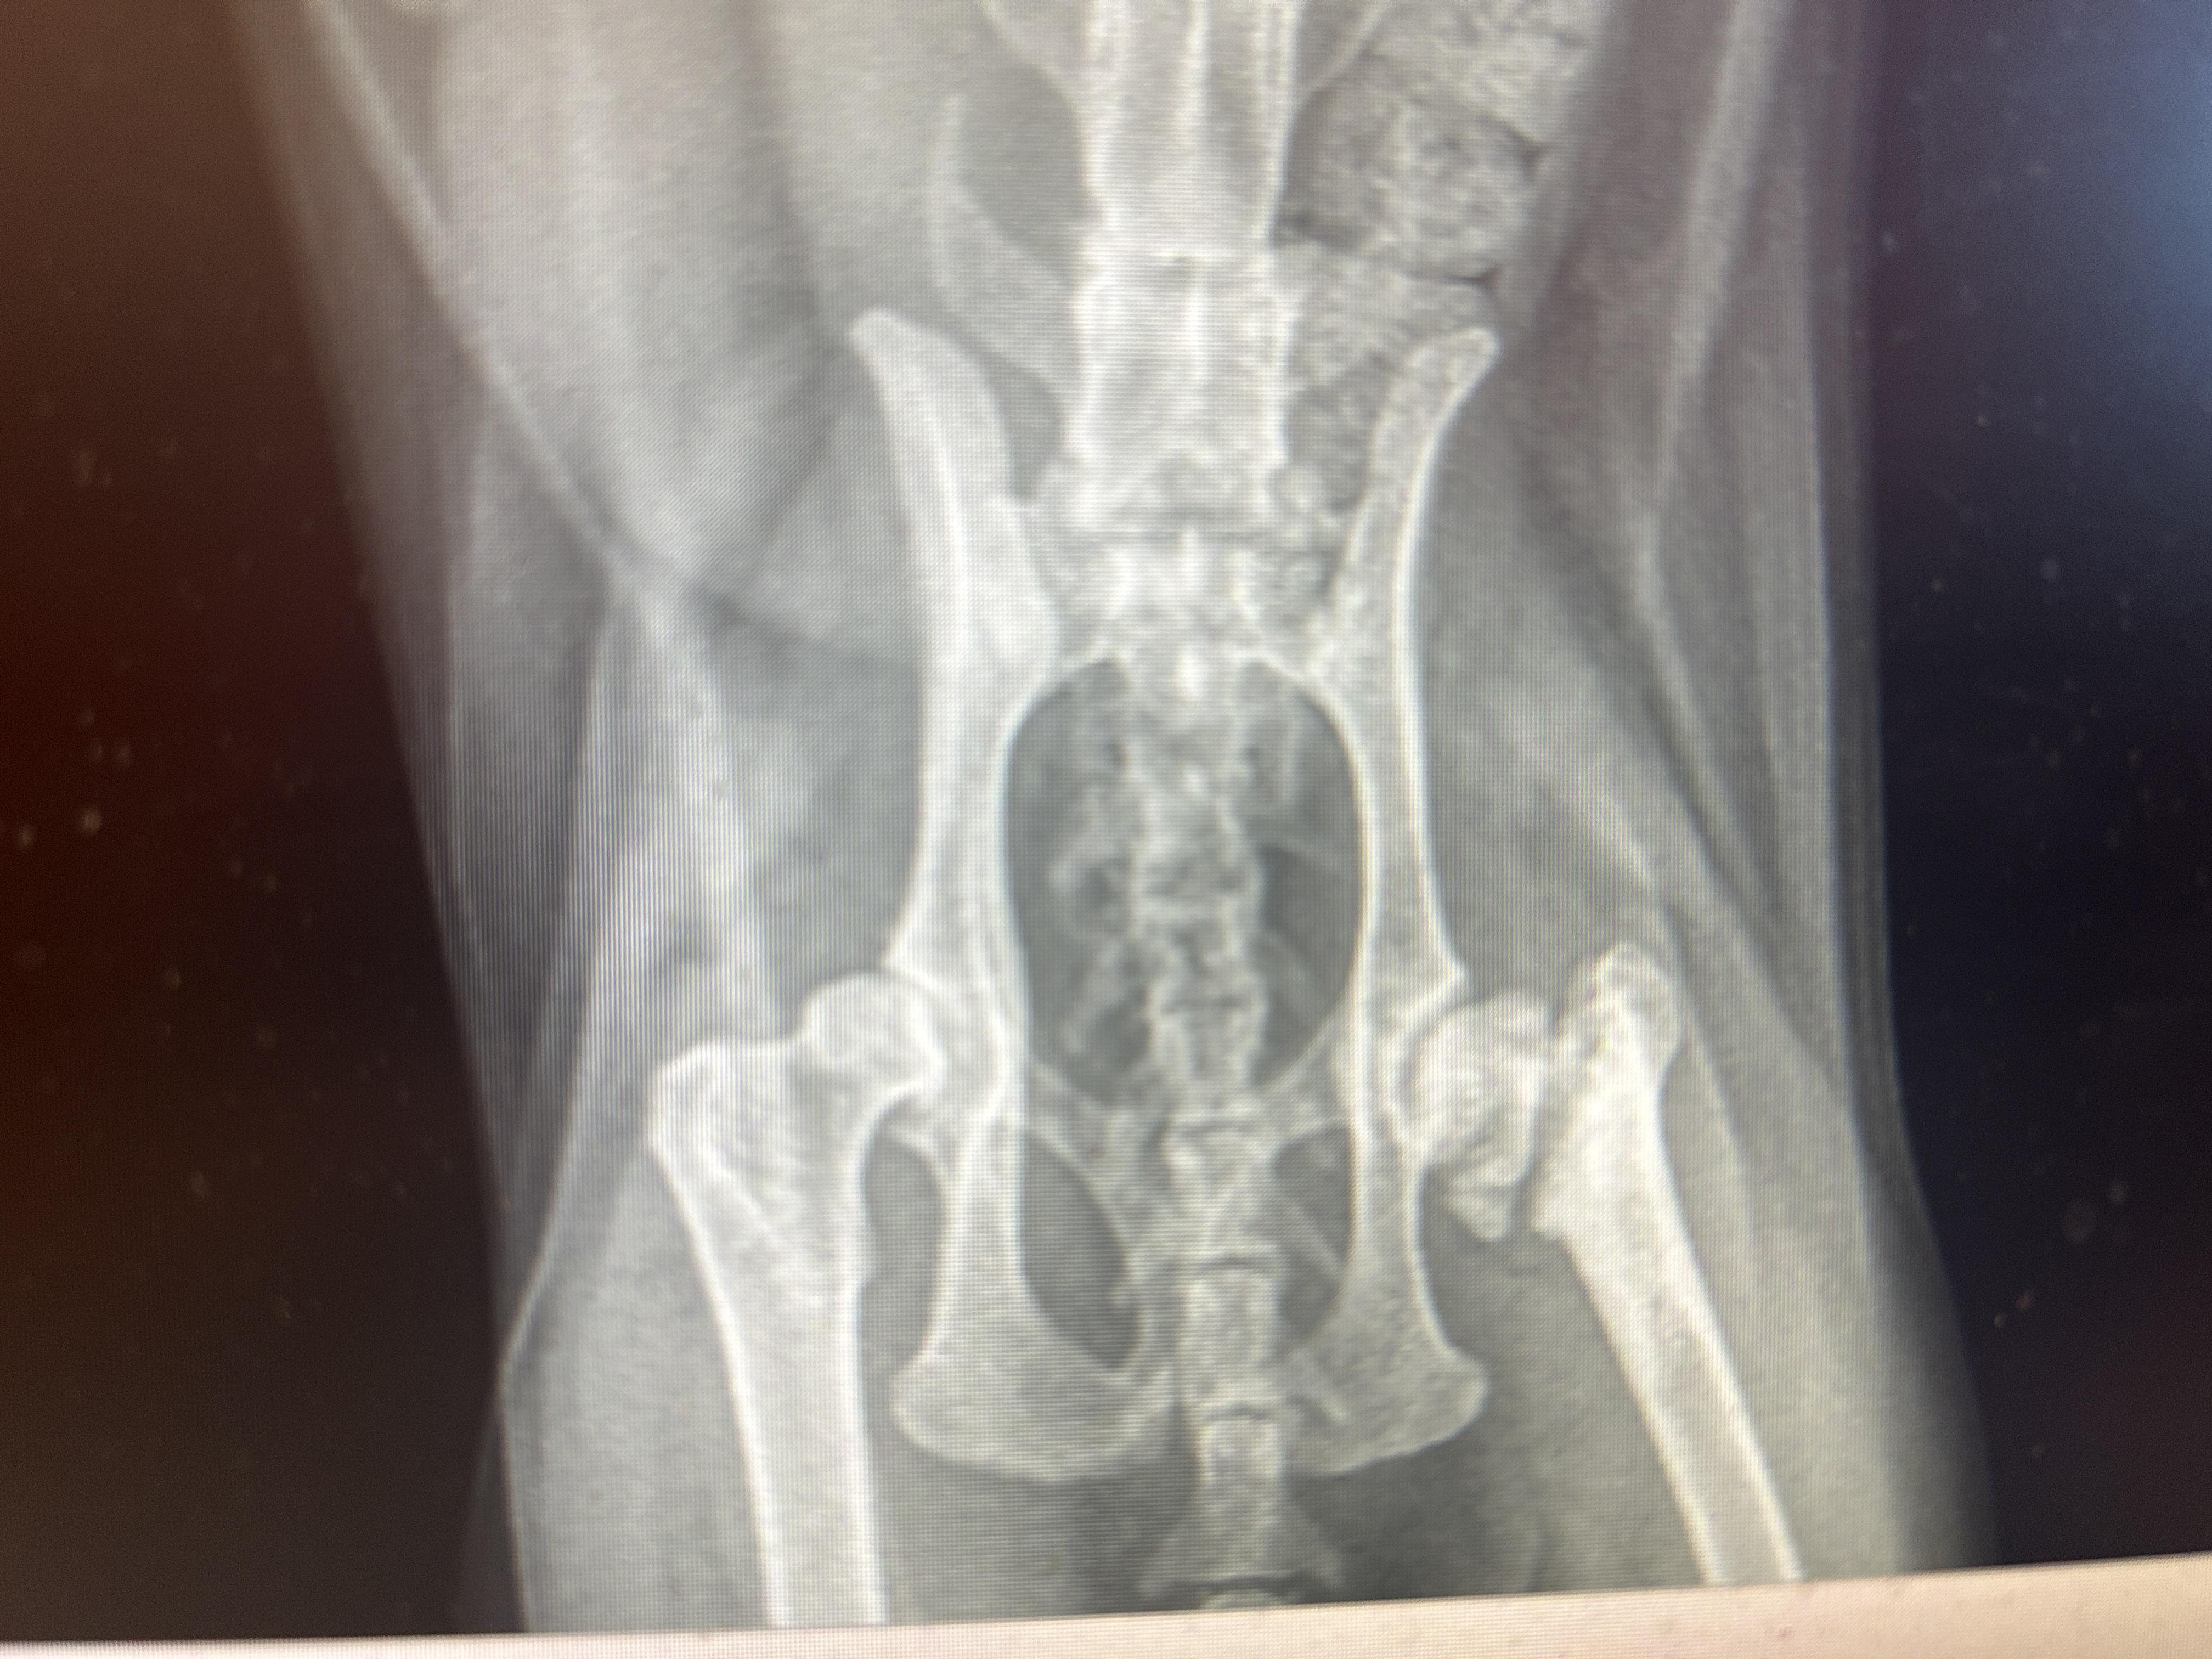

Brad arrived with a few medical concerns that needed attention. He had an oozing wound on his rear end that required antibiotics and was mildly anemic. Imaging also revealed an old right hip fracture in which

Brad arrived with a few medical concerns that needed attention. He had an oozing wound on his rear end that required antibiotics and was mildly anemic. Imaging also revealed an old right hip fracture in which the head of the femur had been completely transected from the neck of the bone. Thankfully, displacement was minimal, so Brad showed no obvious limp and did not appear painful. Over the following four weeks, his wound healed beautifully, his anemia resolved, and he continued to show no signs of discomfort related to the old fracture. Rest assured—should any pain or lameness ever develop, Brad will